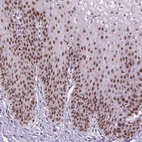

Immunohistochemical staining of human esophagus shows moderate nuclear positivity in squamous epithelial cells.